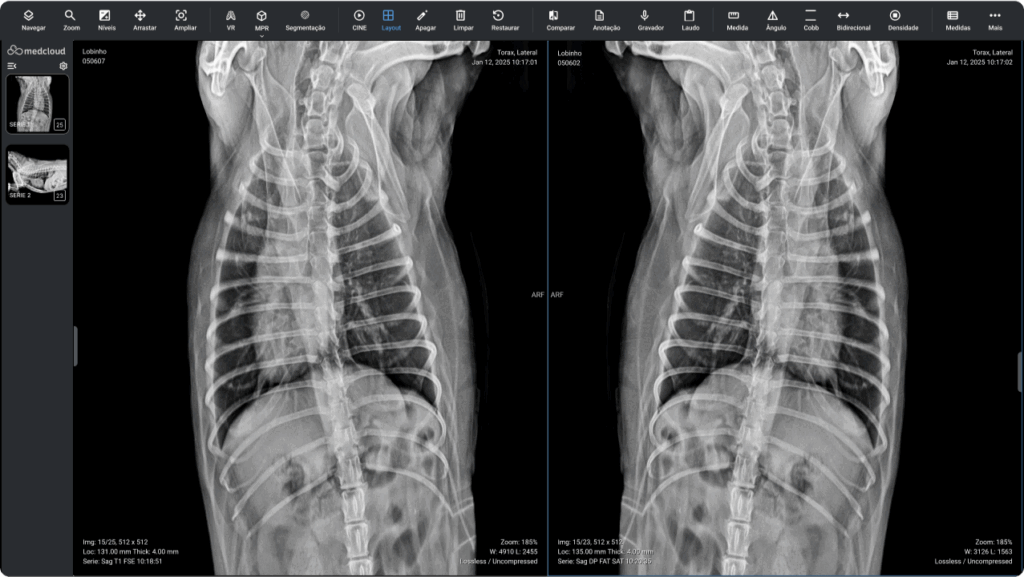

Calidad diagnóstica en cualquier lugar, en cualquier momento y en el menor tiempo posible.

Calidad diagnóstica en cualquier lugar, en cualquier momento y en el menor tiempo posible.

La fusión DICOM PET-CT permite la combinación y sincronización de ambas en una sola imagen o conjunto de datos. Realice análisis más completos superponiendo información metabólica de PET sobre estructuras anatómicas visualizadas por TC para una mejor localización y caracterización de anomalías, como tumores, proporcionando información funcional y estructural en una sola imagen.

Con sólo unos clics y desde cualquier lugar. Trabajo de calidad y seguro en cualquier navegador de Internet.

Accede a los exámenes desde tu computadora de escritorio o usando tu computadora portátil dondequiera que estés. Acceda a informes, archivos adjuntos e imágenes en calidad original, además de todas las herramientas que necesita, dondequiera que vaya.